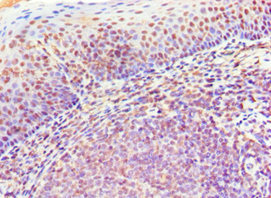

CD20是位于B細(xì)胞上的一種非糖基化磷蛋白,主要在前B細(xì)胞到成熟B細(xì)胞階段表達(dá)。CD20分子屬疏水、4次跨膜蛋白,由297個(gè)氨基酸殘基組成,相對(duì)分子質(zhì)量(Mr)約為33×103。CD20的表達(dá)在不同的B細(xì)胞惡性腫瘤之間是高度可變的 [2-3]。CD20的分子功能與B細(xì)胞受體(BCR)的信號(hào)傳導(dǎo)傾向有關(guān)。CD20被證明與B細(xì)胞上的其他多種表面蛋白(如CD40、CD53、CD81和CD82)相互作用。有研究表明,一些表觀遺傳因子(EZH2、HDAC1/2、HDAC6、Sin3A-HDAC1復(fù)合物)和轉(zhuǎn)錄因子(USF、OCT1/2、PU.1、PiP、ELK1、ETS1、SP1、NFκB、FOXO1、SMAD2/3)也可調(diào)節(jié)CD20的表達(dá) [4-6]。大量研究已證實(shí)CD20是人類B淋巴細(xì)胞表面特異性分子標(biāo)記物,對(duì)B淋巴細(xì)胞的增殖和分化具有調(diào)節(jié)作用。絕大部分的B淋巴細(xì)胞瘤都有CD20的表達(dá),CD20分子易與抗體結(jié)合,且結(jié)合后不易脫落、不內(nèi)化,成為治療B細(xì)胞淋巴瘤的理想靶抗原。目前,抗CD20單克隆抗體是治療B細(xì)胞淋巴瘤(B-cell non-Hodgkin’s lymphoma)的重要靶向藥(圖1) [4]!

圖1. 抗CD20單克隆抗體是治療BCL的重要靶向藥 [4]